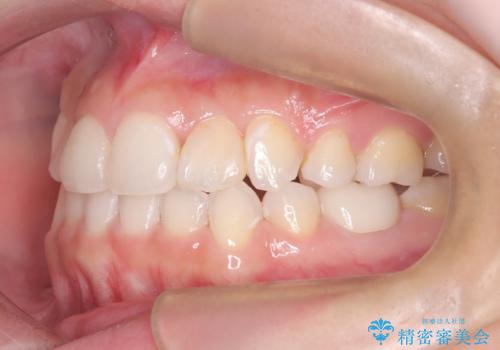

インビザラインによる精密な仕上げ: 全体のがたつきが概ね整った段階で、インビザライン(マウスピース矯正)へ移行しました。透明で目立たないマウスピースを使用しながら、0.1mm単位の細かな歯の配置や、最終的な咬み合わせのバランスを精密に整えていきました。

治療の結果、重度のがたつきは跡形もなく解消され、抜歯したスペースもきれいに閉じました。ワイヤーによる「確実な移動」と、インビザラインによる「緻密な仕上げ」を組み合わせることで、審美性と機能性の両立を叶えた美しい歯並びを実現しました。